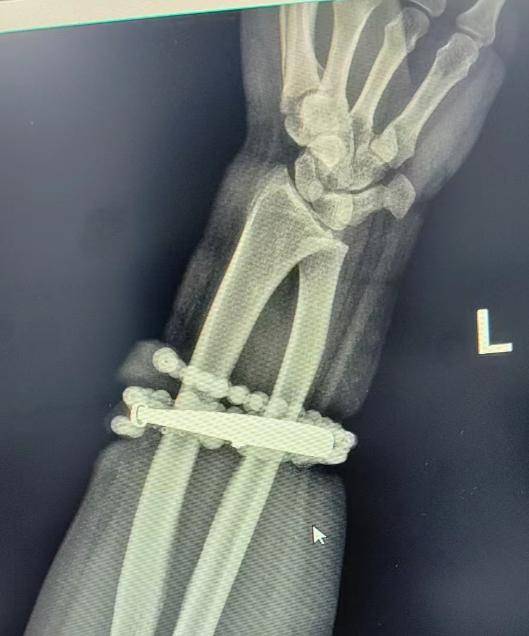

然而,就在两周前,龚女士的情况急转直下:手腕不仅疼痛加剧,还出现了明显的红肿,甚至有脓液渗出登1信用盘代理 。她这才惊觉——手镯和串珠,已经有一部分“长”进了肉里,根本取不下来了!

“这是典型的首饰长期压迫、摩擦,加上细菌感染,引发的慢性炎症和肉芽组织增生登1信用盘代理 。”医生介绍,此时,手镯和串珠已经成了一个不断刺激皮肤、污染伤口的“病灶”,如果不尽快手术取出,感染可能进一步扩散,甚至危及生命或影响手臂功能。

经过一个多小时的手术,医生们将手镯和串珠从厚厚的增生组织中完整剥离出来登1信用盘代理 。目前,龚女士恢复良好,已顺利出院。